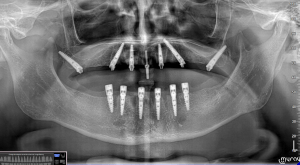

D-r Rafid Hussain, the head dental implant surgeon at Sofia Implant Centre, recently performed the first-ever pterygoid implant surgery in Bulgaria. This achievement follows the trans-sinus surgery recently performed by D-r Hussain and the team of Sofia Implant Centre. This all was made possible through the use of surgical guides and innovative digital protocols, which allowed for highly precise placement of dental implants in the pterygoid bone, providing a secure foundation for a full-arch restoration based on 6 implants (ALL-ON-6).

Our patient, a 62-year-old male, presented with a significant loss of bone density in his upper jaw due to advanced periodontal disease.

Traditional implant solutions were not feasible due to the lack of sufficient bone density and volume in the affected area. That is when we decided to consider the pterygoid implant procedure, utilizing surgical guides to ensure optimal placement and precision.

The pterygoid implant procedure is a groundbreaking procedure which involves placing dental implants in the pterygoid bone, located behind the maxilla, providing a viable solution for patients with severe bone loss in the upper jaw, who would otherwise be ineligible for dental implant treatment. We chose JDPterygo implants from JDentalcare, Italy.

Besides that we used JDnasal implants in the nasal area:

Our use of surgical guides ensured that the procedure was successful, with the patient now able to enjoy a full set of fixed teeth, providing him with increased function, comfort, and confidence.